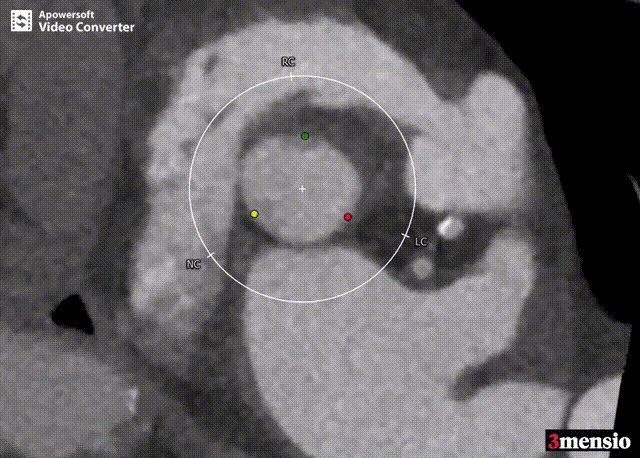

CT评估

术前分析及手术策略

患者瓣膜结构为三叶瓣,无明显增厚和钙化,法式窦结构,双侧冠脉开口高度可。升主动脉增宽,主动脉根部角度78°。主动脉瓣环周径78.8 mm,面积487.9 mm²,平均直径25.1 mm;左冠高度14.7 mm,右冠高度14.7 mm;左室流出道周径26.0 mm,主动脉窦管交界处(STJ)高37.5 mm。

患者年龄较大,主动脉瓣单纯关闭不全,瓣膜锚定难度高,且该病例为典型的“横位心”,瓣膜释放空间较小。与王坚刚、李岩、王胜询、郑帅、孟斐、张春晓教授会诊讨论后,张海波教授团队决定利用3D打印技术,选择27#Ken-Valve瓣膜完成此次手术。